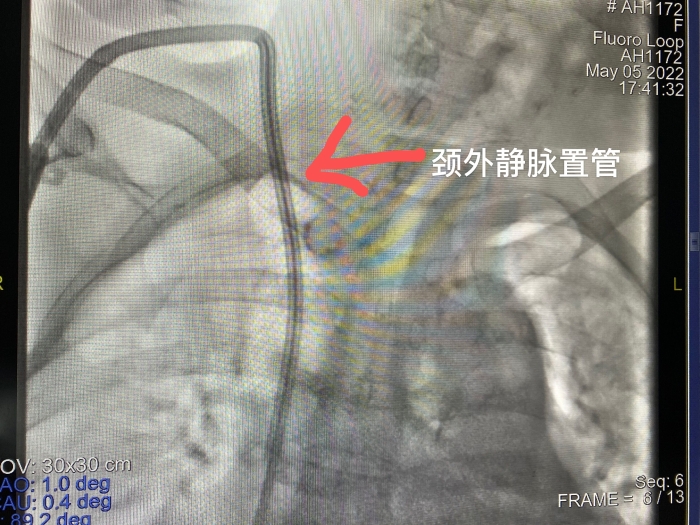

鑒于鄭阿姨目前雙上肢都建立過內(nèi)瘺失敗,右頸內(nèi)靜脈已閉塞,左頸內(nèi)靜脈較細(xì),而鄭阿姨表示不想做瘺了,想安個(gè)導(dǎo)管回去透析等諸多因素,腎內(nèi)科主任胡波經(jīng)過彩超及造影評(píng)估,發(fā)現(xiàn)鄭阿姨右側(cè)頸外靜脈情況還算好,于是胡主任打破常規(guī),另辟蹊徑為其進(jìn)行了右頸外靜脈穿刺置管手術(shù),建立了帶滌綸套的長(zhǎng)期導(dǎo)管。術(shù)后,鄭阿姨的血流量達(dá)到250mL/min,她對(duì)新通路非常滿意,出院后高興地回當(dāng)?shù)蒯t(yī)院繼續(xù)透析了。

頸外靜脈穿刺置管雖然不是最常用的置管部位,但對(duì)于反復(fù)中心靜脈穿刺置管,頸內(nèi)靜脈狹窄或閉塞的患者提供了另一條血管通路途徑。而下肢動(dòng)靜脈內(nèi)瘺的開展對(duì)于上肢血管條件不佳、存在中心靜脈狹窄或閉塞的長(zhǎng)期透析患者開辟了另一條新的透析生命線,解決了血管耗竭透析患者的一大難題。攀鋼總醫(yī)院不斷提高的血透通路技術(shù)為攀西地區(qū)廣大血液透析患者帶來了更大的福音。